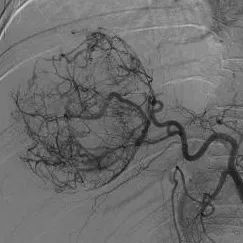

患者被送入导管室后,郑胜与放射科主治医师苏维杰第一时间开始经股动脉肝动脉造影与栓塞术。术中用碘化油及明胶海绵颗粒对出血动脉进行了栓塞,成功止血。

术前

郑胜介绍,相较于急诊开腹止血手术,介入栓塞术具有创伤小、恢复快、并发症少等优势,能最大限度地保护肝功能。

同时,血管造影能进一步明确肿块大小、范围及血管情况,为接下来的治疗提供依据。